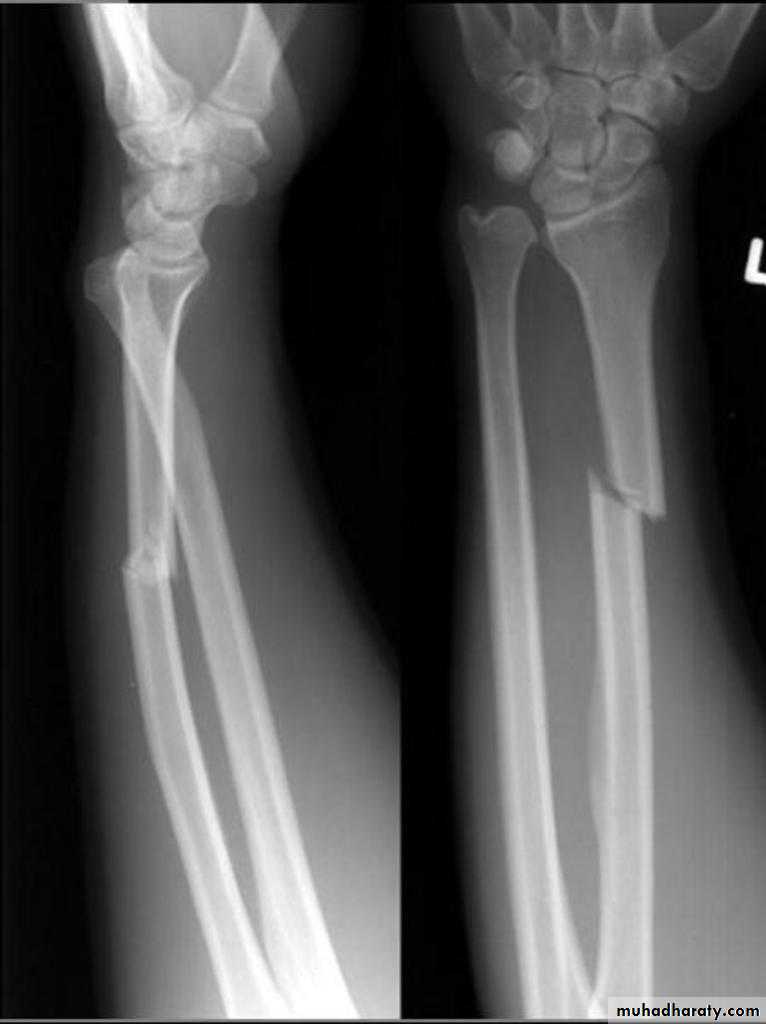

Upper limb

Fall on out stretched hand

xray